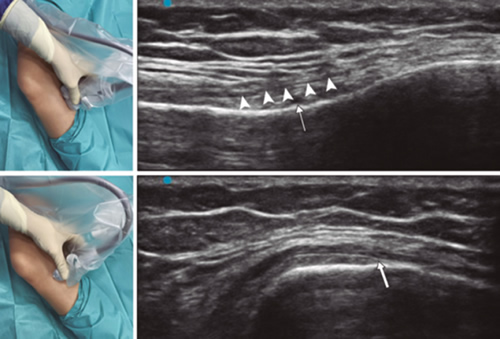

Para ubicar al NGIM (Figura 4) colocamos el transductor en un plano coronal sobre la cara interna de la rodilla, lo deslizamos en sentido caudal hasta identificar la unión de diáfisis con la metáfisis tibial y la arteria/nervio geniculado inferomedial (ANGIM), y repetimos los mismos pasos que usamos para el NGSM. En caso de no encontrar la ANGIM, la referencia que se tomará será la profundidad del 50 % del espesor de la tibia (14,16,19).

Fig. 4. Sonoanatomía y técnica para realizar el bloqueo del nervio geniculado inferomedial (NGIM). El transductor se ubica en el eje largo proximal de la tibia e identificamos el paquete vasculonervioso del NGIM (flecha) justo debajo ligamento colateral medial (puntas de flechas). Luego se gira la sonda 90 grados para obtener una visión en eje corto de la tibia (no olvidar mantener la misma profundidad a la que encontramos el NGIM en el eje largo).